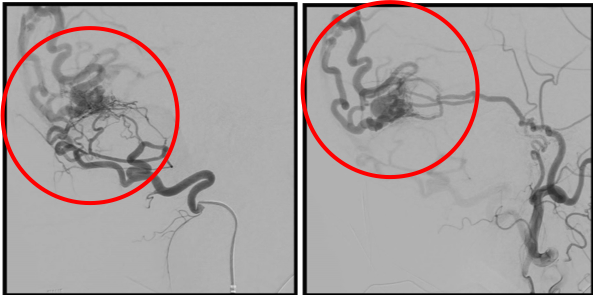

破裂内頚動脈瘤

術後の造影写真です。主幹動脈は温存できており、動脈瘤は造影されなくなっています。

術後4週間、動脈瘤の再発はありません。

術後6か月、動脈瘤は完全に消失しています。